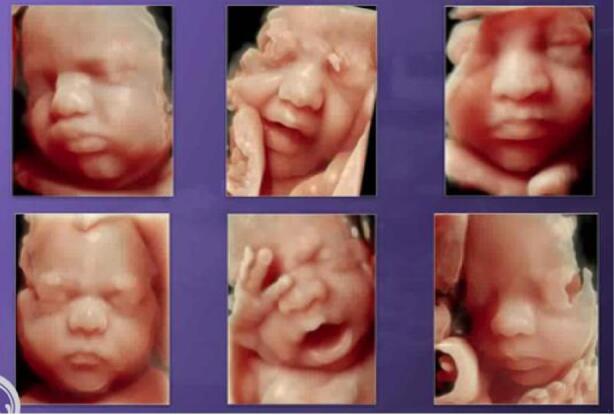

中孕期彩超胎儿颜面部及脊柱成像,把胎儿看的真真切切,明明白白,让您提前观察到宝宝的一举一动,一颦一笑,准妈妈们可以亲眼目睹胎儿在子宫内的相貌和动作,在感叹生命发生的同时,留下一段珍贵的影像,一段属于您和宝宝最早最珍贵的回忆。

故三维、四维容积超声对诊断胎儿神经系统学,表面成像的胎儿畸形的筛查有更直观的感受,更明确的帮助诊断。